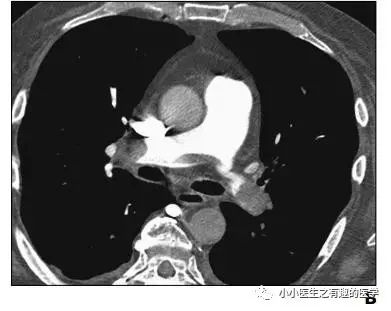

其实,我大中华也有医生用CT平扫发现可疑肺栓塞。

下面是上海交通大学的论文

基本上看得到。

3.吴世明, 陈龙兴, 唐震. CT平扫在急性肺栓塞中的诊断意义[J]. 医学影像学杂志, 2017, 27(4):652-655.